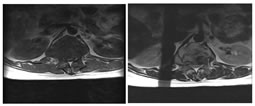

A: SAGITTAL T1W; B: SAGITTAL T2W; C: SAGITTAL STIR

D: AXIAL T1W; E: AXIAL T2W

Figure 4: 32 year old male presenting with back ache for 2 months with bilateral lower limb weakness. Kyphotic deformity at thoracolumbar junction due to collapse of T12 and L1 vertebral bodies with near complete obliteration of the intervertebral disc space (A,B,C). Intervertebral discal collection seen with collections also noted in bilateral paravertebral regions, psoas muscles and epidural space with compression over the distal cord (D,E)